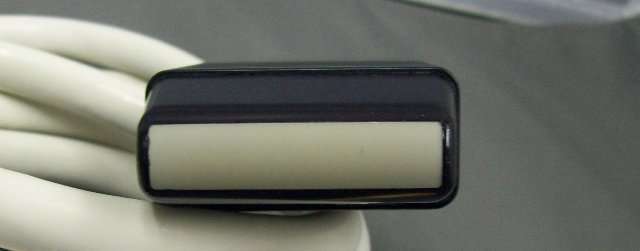

Acuson Linear Ultrasound Probe 7L3 08267217

Sale price$ 3,837.58